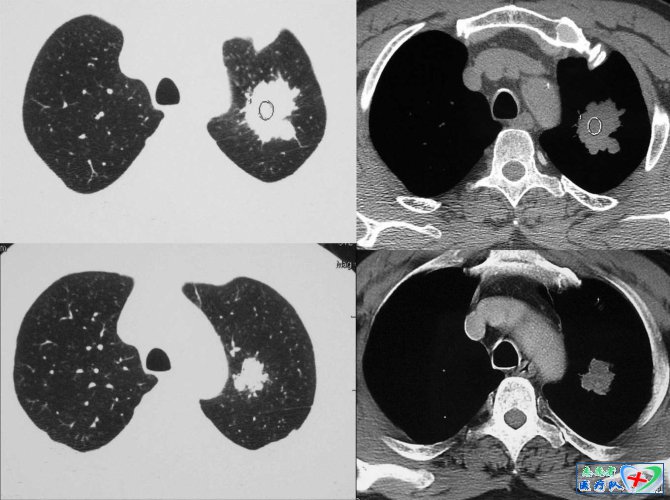

6、分叶征

众所周知,这是周围性肺癌的一个比较特异的征象,结节边缘凹凸不平的分叶状轮廓,是该征的主要表现。分叶征有深分叶、中分叶及浅分叶之分,以弦弧距和弦长之比来衡量:比值≥0.4为深分叶;浅分叶≤0.2;比值=为中分叶。这样划分的意义在于界定肿瘤的良恶性质,一般深分叶多是恶性肿瘤,对于肿块达3~5公分的肿瘤,分叶多较大、较明显,因而恶性度也很高;而分叶较大且浅者,多见于良性肿瘤或其他量性肿块。分叶形成的机制有下属几方面的原因:一是肿瘤生长的速度;而是肿瘤受周围组织或器官的阻挡和限制(在肺癌的大体标本切面上,常可见到小叶间隔的纤维增生,形成对肿瘤组织生长有限制作用);三是肿瘤突破小叶间隔向外扩展并和邻近的相互合并进而形成较大的分叶。